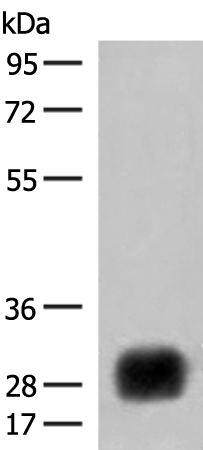

分类: 科研抗体货号: P09880别名: PDIR应用: WB,IHC反应种属: Human, Mouse, Rat

分类: 科研抗体货号: P09886别名: CHED; CHED1; CHED2; PPCD1; ZNF339; EUROIMAGE566589应用: WB,IHC反应种属: Human, Mouse